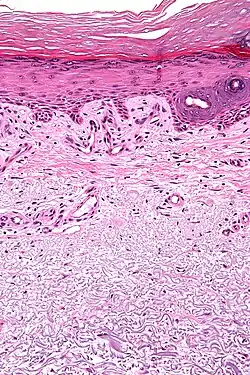

Micrograph showing solar elastosis - grey, jumbled spaghetti-like material on bottom of image. H&E stain. | |

In the earlier stages of actinic elastosis, elastic fiber proliferation can be seen in the dermis. As the condition becomes more established, the collagen fibers of the papillary dermis and reticular dermis become increasingly replaced by thickened and curled fibers that form tangled masses and appear basophilic under routine haematoxylin and eosin staining. These fibers stain black with the Verhoeff stain.[2]